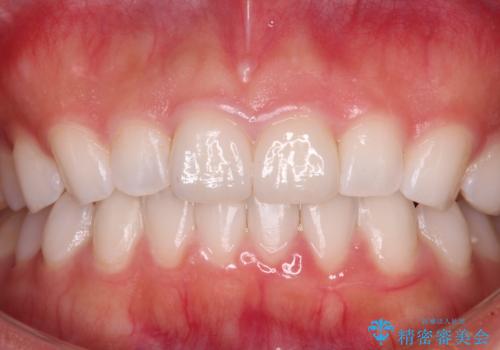

- 矯正治療で歯列を整えた後、前歯の形が気になった患者様です。

矯正前の歯列の影響で、前歯の先端が非対称にすり減ってしまったため、矯正治療後の形が非対称になっていました。

むし歯はなく、矯正治療で咬み合わせが改善していたので、侵襲量の少ないラミネートベニアにて治療することとしました。